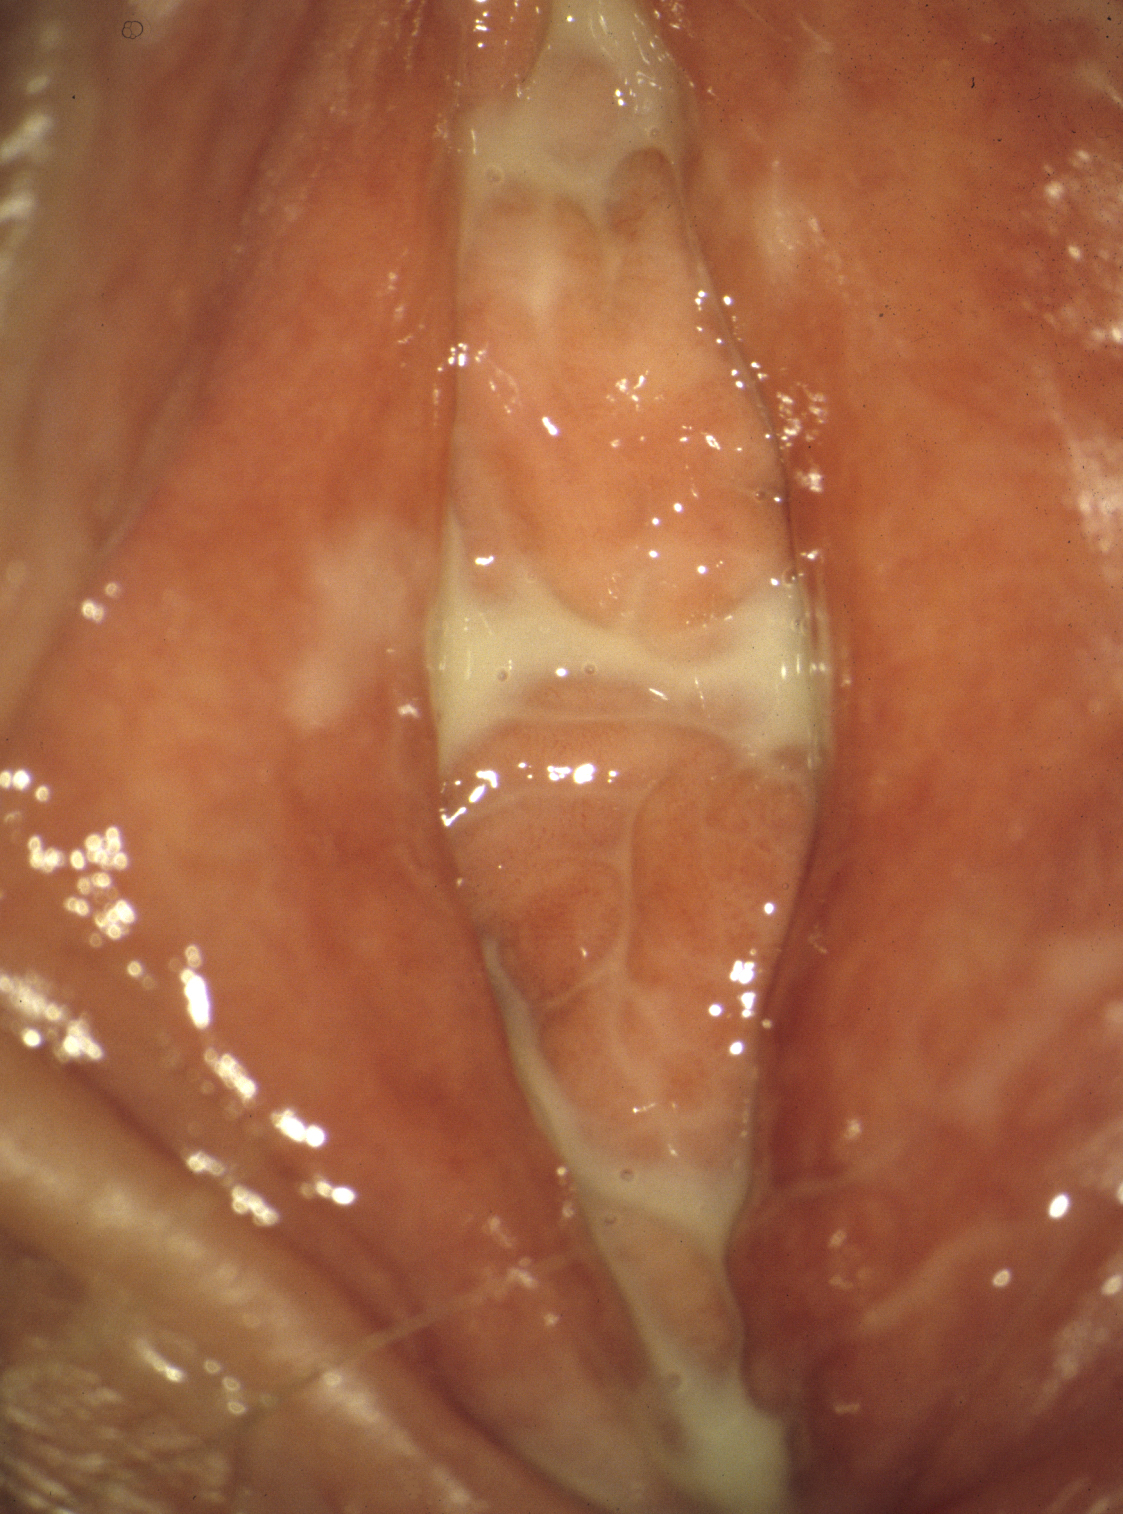

This is the most common itchy, inflammatory, non-infective dermatosis of the vulva and does not occur just in older age, but also in young girls (Figure 2). The diagnosis of the early stage is particularly important in young women. Occasionally, only effects of scratching, like slight hemorrhages and skin damages are visible.

Typical early signs are the persistent itching, which occasionally may not exist, and the whitish alterations on the small labia. The constrictions of the clitoris and later on the introitus are a very typical sign of a lichen sclerosus (Figure 3). Co-involvement of the area around the urethral opening is rather rare. A biopsy is necessary only in the early stage or in the absence of clinical experience.

Figure 3: Lichen sclerosus in a 36-year-old women (© Eiko Petersen)

The recommended therapy today consists mainly of corticosteroid ointments. In the beginning highly effective corticosteroids, e.g. clobetasol, are preferred. Since it is a chronic disease, repeated treatments are almost always necessary. For this purpose, less atrophic corticosteroids, for example clobetasol, may also be used. Often, in the early stage an interval therapy for 1 to 2 weeks is sufficient. Regular, multi-day care with greasy ointments is essential and saves corticosteroids. Testosterone has been obsolete for years. The immune modulators tacrolimus and pimecrolimus do not cause atrophy, but are less effective.